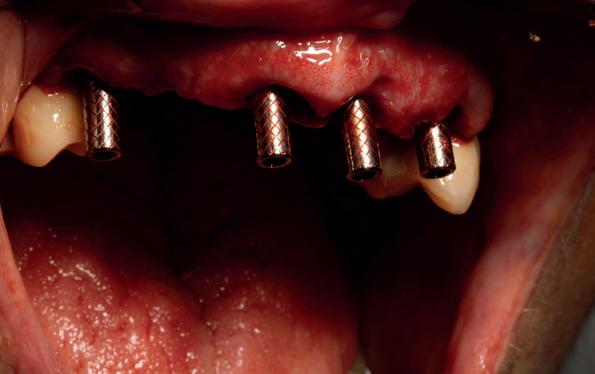

5. Implantaten geplaatst op geleide van een boorsjabloon; botopbouw met sinuslift volgens de GBR-techniek en Caldwell Luc methode; materialen: Oragraft & BioOss, Ossix membr, hyaluronzuur. In de BK is gekozen voor Bego implantaten (Bego SC en RSX 3,75x 11,5 & 13mm).

6. In het front zijn Bego 3,25mm

Tijdens de chirurgische behandeling worden na het afschuiven van de flap de posities bepaald van de implantaten met de boorsjabloon. In de bovenkaak worden 7 implantaten geplaatst en in de onderkaak 8

implantaten geplaatst terwijl in de zijdelingse delen voor een bredere diameter (3,75 & 4,1) is gekozen, met lengte 8,5 en 10mm.

7. OPT na abutmentchirurgie 6 maanden later. De integratie van de implantaten met de botopbouw & sinusliften verloopt voorspoedig.